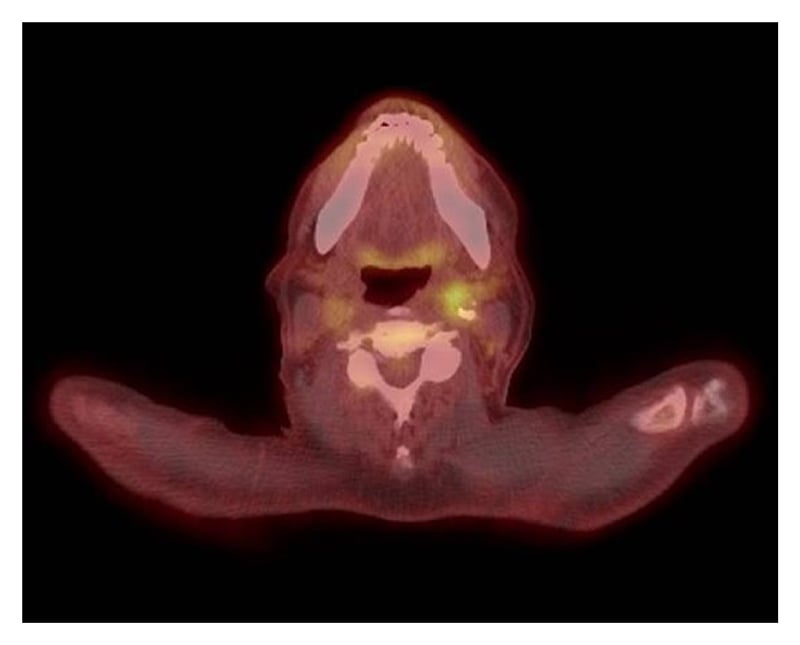

Magnetic resonance angiography (MRA) of the head and neck showed soft-tissue thickening of the distal left common carotid artery and left carotid bifurcation (Figure 1). A positron emission tomography (PET)-CT scan identified asymmetric moderate activity of the tracer fluorodeoxyglucose (FDG) along the medial aspect of the left common carotid artery (Figure 2). Skipped areas of mild uptake were also noted along the thoracic aorta wall.

Figure 2: PET-CT scan shows asymmetric hypermetabolic activity along the left common carotid artery.